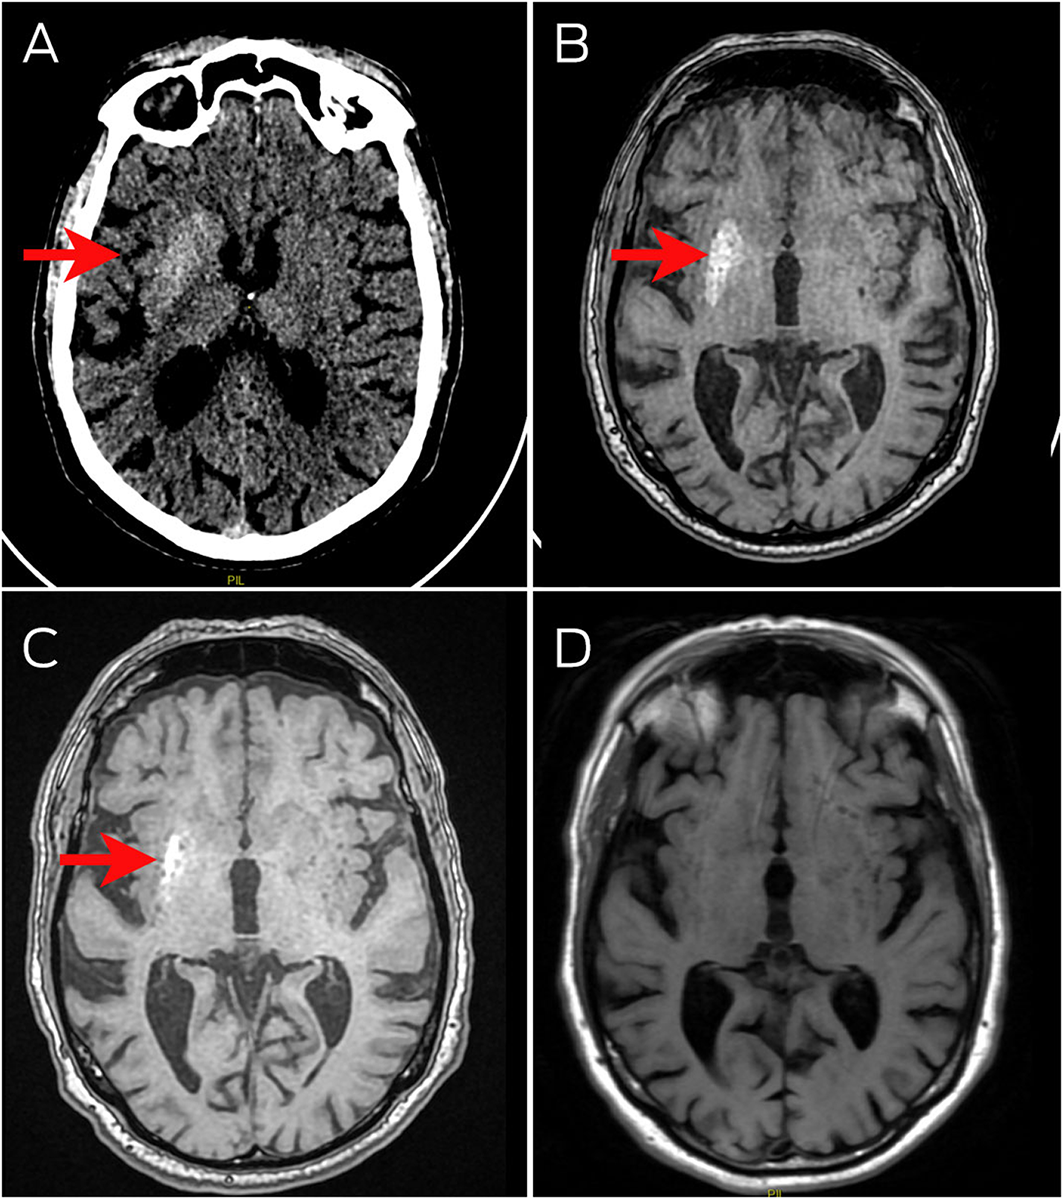

- 1. Chua CB, Sun CK, Hsu CW, et al. “Diabetic striatopathy”: clinical presentations, controversy, pathogenesis, treatments, and outcomes. Sci Rep 2020; 10: 1594.